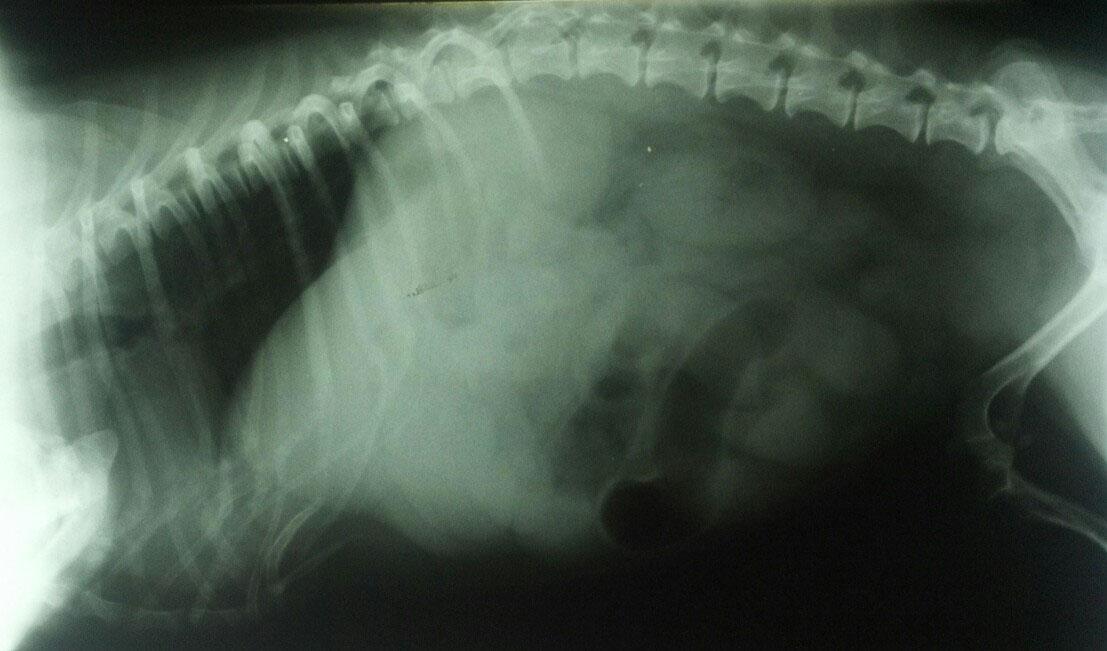

The patient is a 13 year old spayed female Dachshund dog which was presented for four days of anorexia and vomiting. She was given Cerenia, which helped, but still had ileus. Dog has vomited carpet material in past. Spec cPL was normal. Radiographs revealed dilated intestine, which appeared to be colon and cecum.